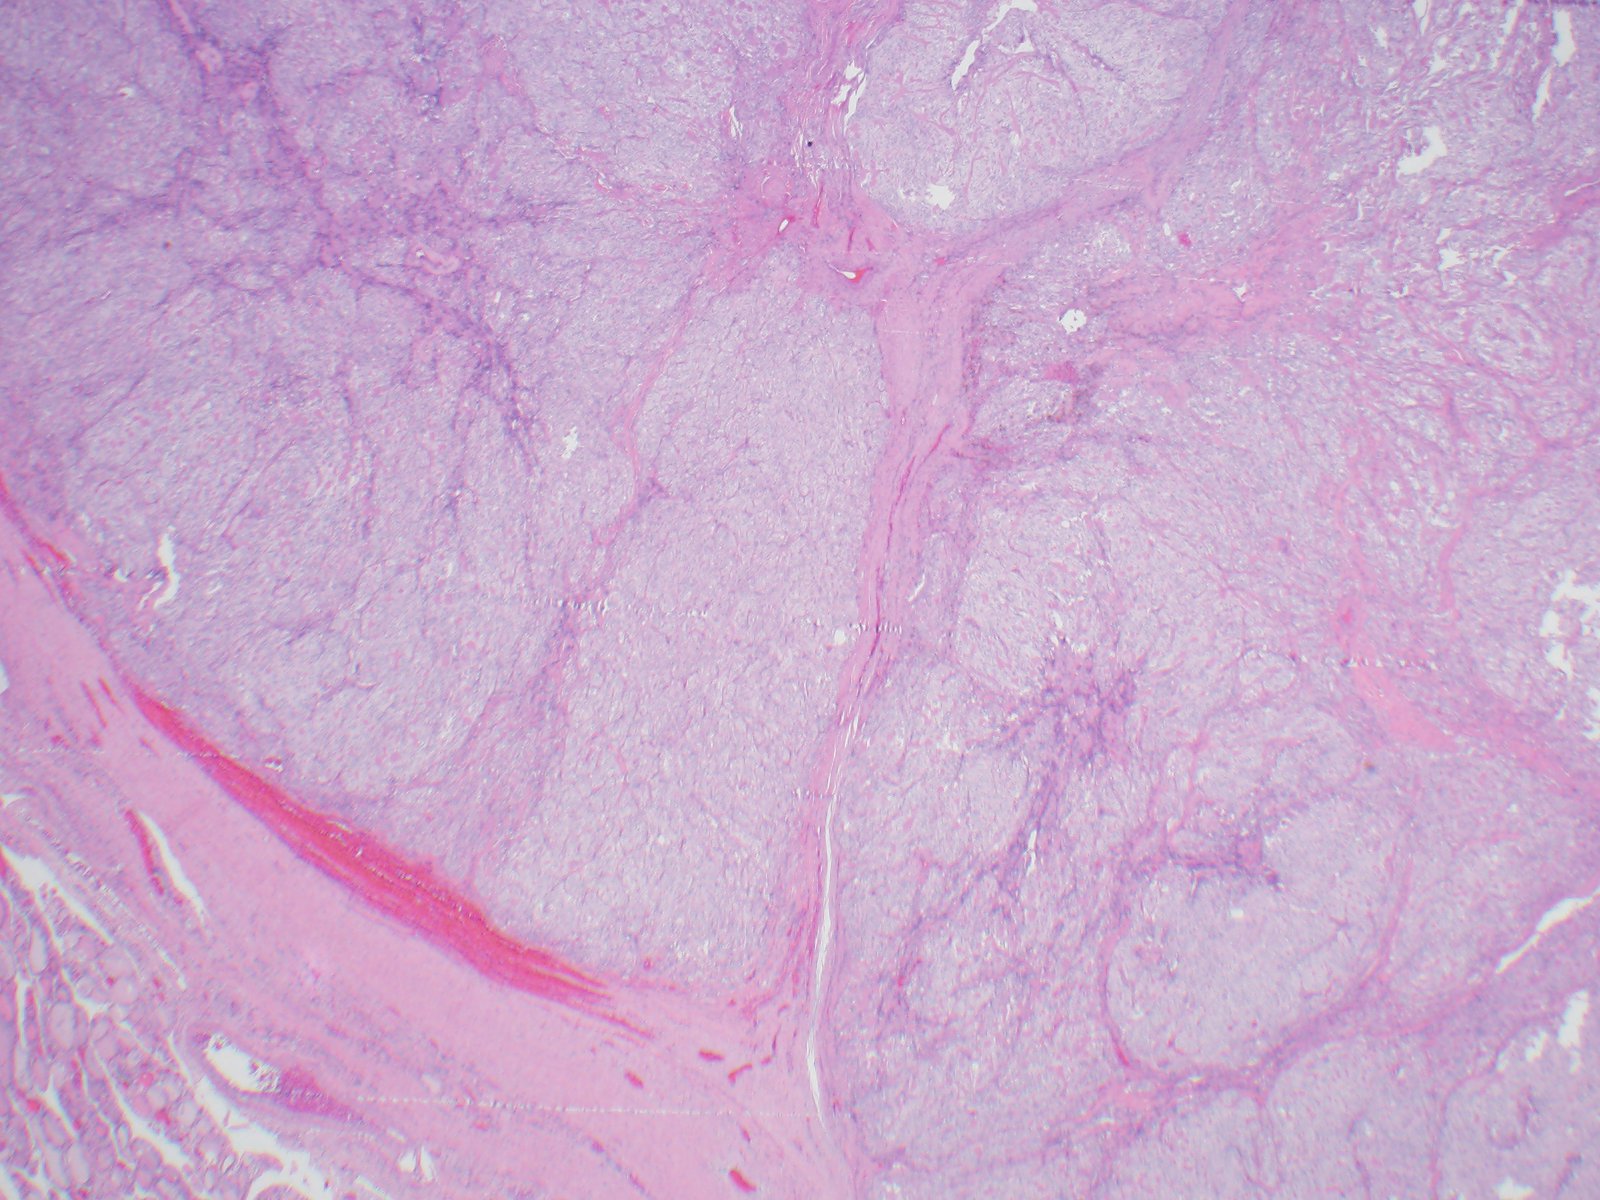

An original diagnosis of medullary carcinoma was rendered. There was insufficient material for cellblock, therefore the patient underwent serologic testing. Calcitonin and CEA levels were normal, which prompted a conversation with the endocrine surgeon to determine best course of treatment for the patient. An Afirma vial was available, and was sent for molecular analysis, which showed a PAX8/GLIS3 rearrangement. Taken together with the morphology, the serologic findings and the molecular result, the final diagnosis was hyalinizing trabecular tumor (in this case, mimicking medullary thyroid carcinoma). Lobectomy was subsequently performed, which confirmed the original cytologic diagnosis.

HTT of the thyroid is a rare follicular derived neoplasm that occurs more commonly in middle-aged euthyroid females, incidentally found. They have a characteristic rearrangement of GLIS and have a favorable prognosis. Cytologically, the cells resemble papillary thyroid carcinoma, medullary thyroid carcinoma and non-invasive follicular thyroid neoplasm with papillary-like nuclear features. On surgical pathology, HTT exhibits a prominent trabecular pattern, abundant intratrabecular hyalinized stroma and characteristic nuclear features of papillary carcinoma.